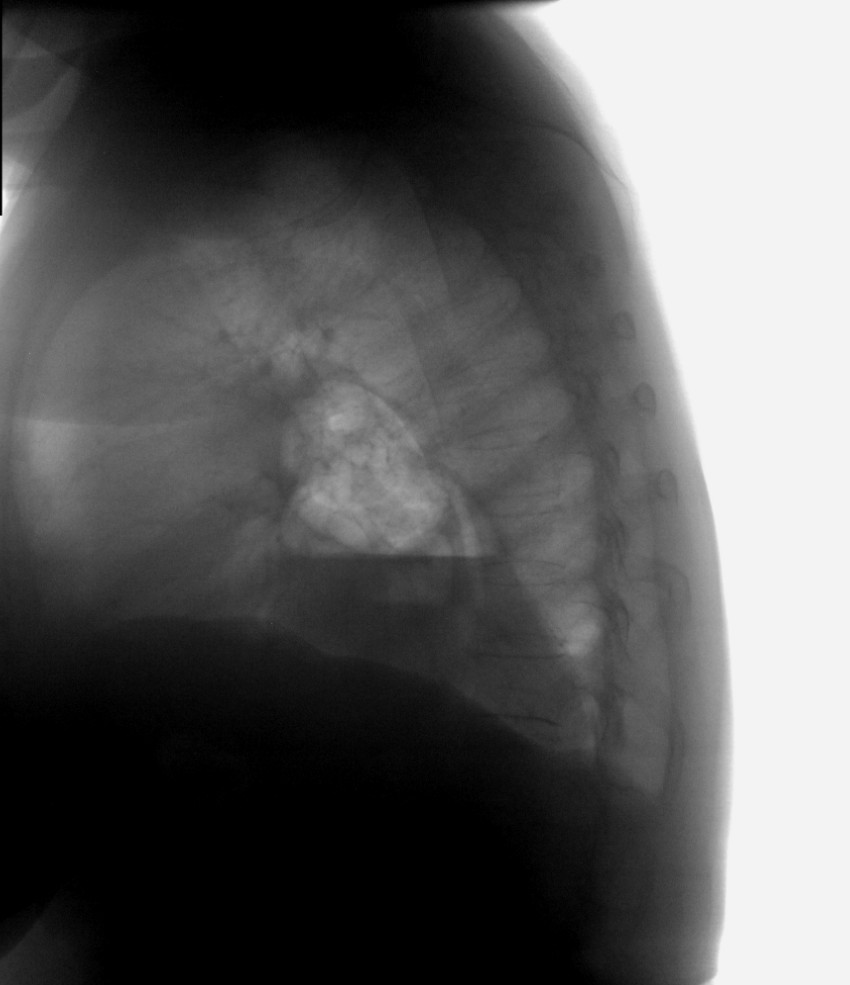

Грыжа пищеводного отверстия диафрагмы.

Может и без грыжи. Внутригрудной желудок. Нужно конрастировать пищевод.

Конечно, Вы правы Петрович, может и "грудной" желудок